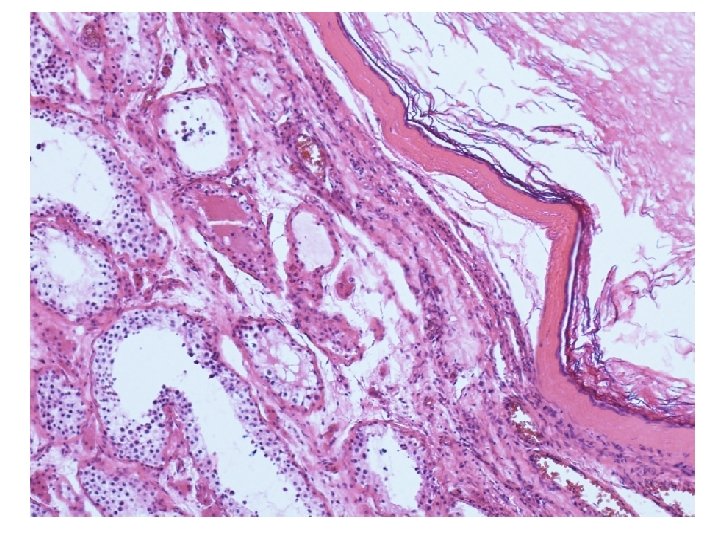

Mikroskopické vyšetření • tkáň varlete se stěnou cysty tvořenou různě silným hyalinizovaným vazivem s různě intenzivní kulatobuněčnou zánětlivou celulizací, která je ložiskově vystlaná zachovalým rohovějícím vrstevnatým dlaždicovým epitelem • v lumen cystického útvaru keratinové hmoty • v okolí cystického útvaru atrofické a hyalinizované semenotvorné kanálky

teratom prepubertálního typu (nezávislý na intratubulární germinální neoplázii), tzv. epidermální cysta